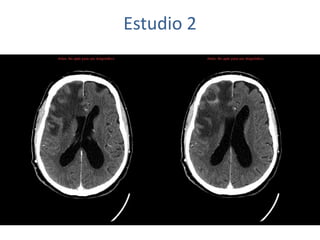

Estudio 2

• Estudio sin y con contraste, con reconstrucciones sagitales y coronales

del estudio con contraste.

Se observa una lesión ocupante de espacio en lóbulo frontal derecho que

presenta un tamaño de 18 x 32 x 22 mm (cc x ap x tr), bilobulada, no del

todo bien delimitada, con realce en anillo irregular, con hipocaptación

central, probablemente por necrosis, y asociada a un extenso edema

vasogénico con efecto masa tanto sobre los surcos de la convexidad

como sobre la cisterna insular, el sistema ventricular y la línea media,

esta última con un desplazamiento de 5 mm a la altura del septo

interventricular.

No se aprecian otras lesiones focales intra o extraaxiales de significación

patológica.

Habría que considerar como primera posibilidad que se tratase de una

lesión metastásica, por bien un tumor primario, aunque no se puede

descartar otras opciones, sin imprescindible correlación con la clínica y

con sus antecedentes.